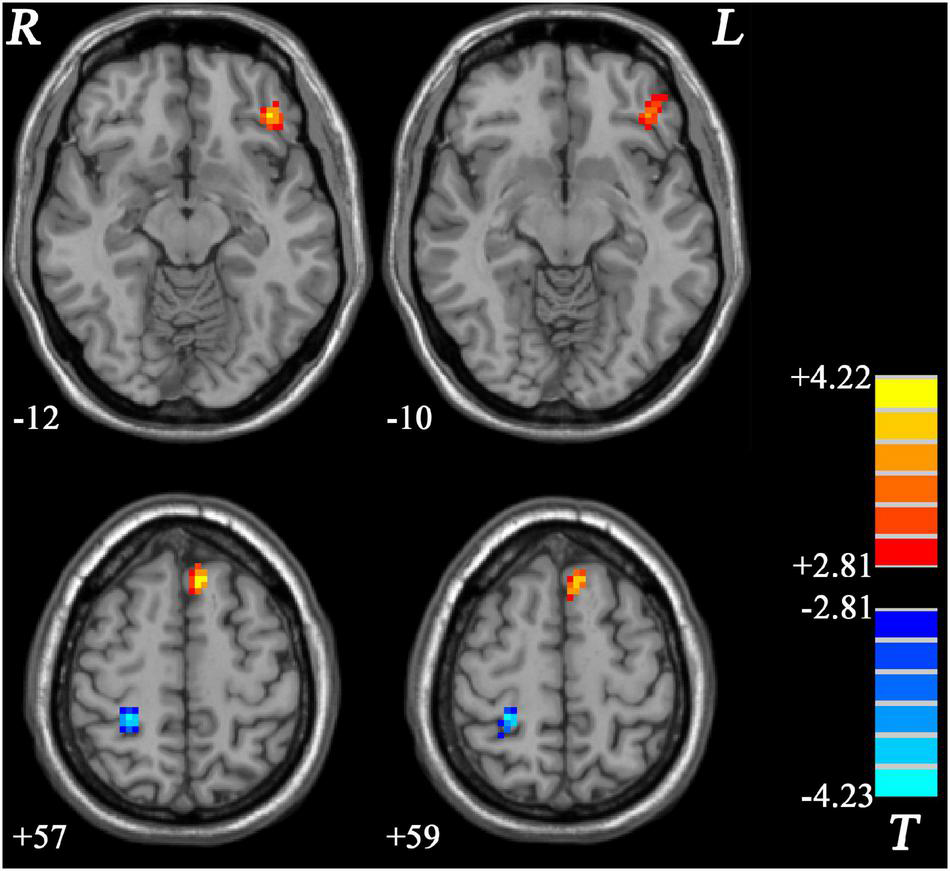

Similar to GI-MDD group, increased PAS scores were found in the left PCC/precuneus in nGI-MDD patients relative to HCs. Decreased PAS scores were displayed in the bilateral superior MPFC, left IFG, and left insula (Table 2 and Figure 4).

Figure 4. Regions with significantly different PAS scores in nGI-MDD patients compared to HCs. The color bar indicates the T-values from post hoc t-tests. HCs, healthy controls; nGI-MDD, major depressive disorder without gastrointestinal symptoms; PAS, parameter of asymmetry.

This study investigated the effect of GI symptoms on functional asymmetry in first-episode, treatment-naive MDD patients. In comparison across three groups, we found that the regions with significant differences were dominantly distributed in the left hemisphere and involved multiple brain networks including the DMN, visual network, frontoparietal network, and cerebellum. Increased PAS scores in the left IFG and left superior MPFC and decreased PAS scores in the right postcentral gyrus were found in comparison between GI-MDD and nGI-MDD patients. The PAS scores of the left IFG and left superior MPFC were correlated with the severity of GI problems and, more importantly, they could better meet the requirment of discrimination between GI-MDD and nGI-MDD patients. In addition, increased PAS scores in the PCC/precuneus were found in both GI-MDD and nGI-MDD patients.

In both GI-MDD and nGI-MDD groups, we found increased PAS scores in the left PCC/precuneus. A previous study of our group using a large sample dataset from the REST-meta-MDD project, the largest MDD resting-state fMRI database, also reported increased PAS scores in the left PCC and precuneus (Ding et al., 2021). These results suggested stronger interhemispheric FC and/or weaker intrahemispheric FC in the left PCC and precuneus in MDD patients. Most studies using VMHC found decreased homotopic connectivity in the PCC and precuneus in MDD patients (Guo et al., 2013; Fan et al., 2018; Shan et al., 2021), though some increased VMHC was reported (Zhao et al., 2021). The inconsistency between these findings and our results might result from different analysis method. The focuses of VMHC and PAS were different. Specifically, the former shows an interest in abnormal interhemispheric FC and only limits to homotopic voxels, whereas the latter expresses interest in the change of functional lateralization. Therefore, it is not surprising that these findings pointed to conflicting results. Both PCC and precuneus are key regions of DMN and were implicated in the introspective processes (Broyd et al., 2009). The altered functional asymmetry in PCC and precuneus suggested less lateralization of these regions in depression.